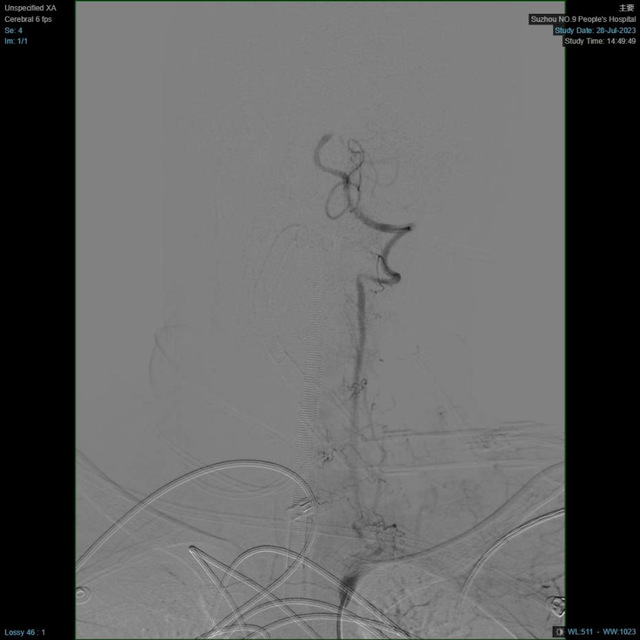

DSA手术室

患者的血管情况远比预计的复杂,维持生命意识的最主要的血管——基底动脉主干发生了闭塞,这样的病变可引起肢体瘫痪、昏迷、甚至死亡。这种手术病变复杂,手术时间长,再通率低,对医生的体力和技术经验都是极大的挑战。医护团队密切协作配合,手术有条不紊地进行,迅速实施脑动脉取栓术。经过2小时的抢救,患者堵塞的血管终于被成功打通,左侧肢体活动明显增多,而此时没有人注意到,手术医师20多斤的铅衣压在身上长达几小时,已经全身湿透。